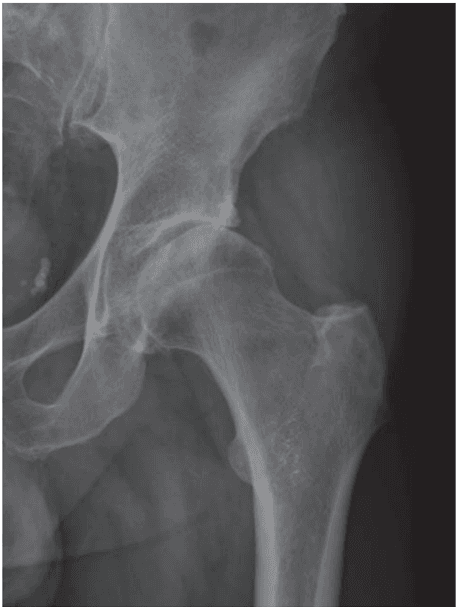

Is intra-articular injection of autologous micro-fragmented adipose tissue effective in hip osteoarthritis? A three year follow-up

Micro-fragmented Adipose Tissue Transplantation (MATT) for the treatment of acetabular delamination. A two years follow up comparison study with microfractures

Mesenchymal Stem Cells injection in hip osteoarthritis: preliminary results